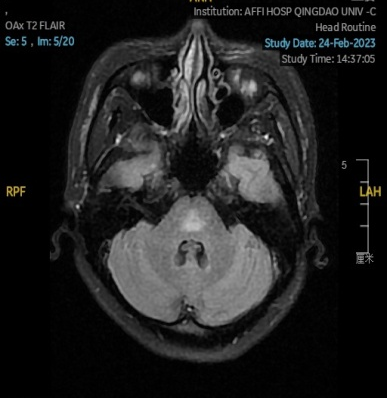

2023.02.24颅脑MR平扫示双侧基底节区及桥脑异常信号,考虑渗透性脱髓鞘综合征,见图3。

图3 2023.02.24颅脑MR成像示双侧基底节区及桥脑见对称性片样长T1长T2信号,FLAIR呈高信号。脑室、脑池、脑沟、脑裂未见明显异常。中线结构居中。

图片